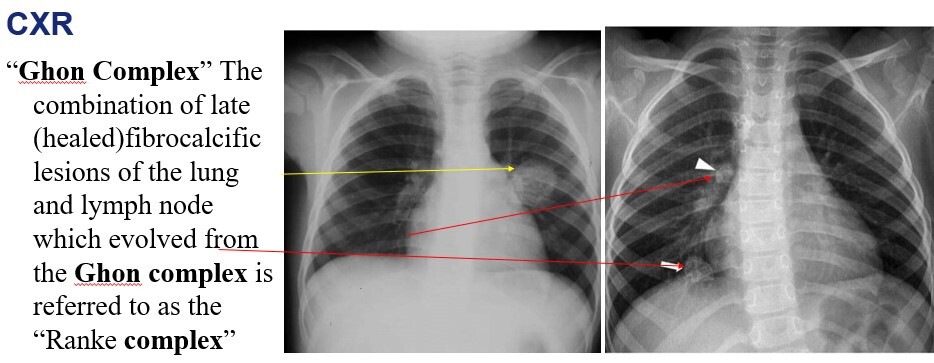

TB CXR looks like what?

Apical cavitation with calcification and hilar lymphadenopathy

What does TB look like when its healed?